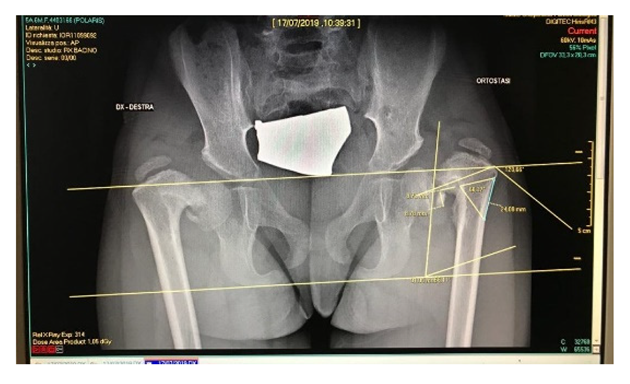

Seven different cases are reported in this study to verify the effectiveness of the CASS methodology and to identify any criticalities deriving from the great cases of pathology in the orthopedic field (Table 2). For all patients, the processing starts from a computerized tomography examination to obtain an optimized 3D model of the examined anatomy and, finally, the simulation of the surgery on CREO.

The CASS process was achieved agreeing to the surgeons’ likings and experiences; thus, patients were not consecutive and the study was not randomized. Parents and carers provided authorization for the study. The methodology described and illustrated by the example of a Monteggia lesion has been applied to all the cases reported in Table 4. This resulted in seven different assembly files on CREO, each one representing the phases of the respective surgery. Applying simulation to more than one pathology, involving different body segments, has enabled its effectiveness to be verified and the problems to be solved or improved. Some of the cases have already been operated and the surgeons of Rizzoli were very satisfied with the results obtained in the pre-operative planning phase, finding a considerable reduction in risks and timing during the operating phase.